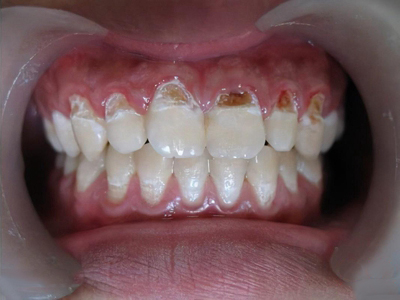

酸蚀症牙齿缺损伴有褐色斑块图

酸蚀症会导致患者门牙牙齿切缘出现缺损,缺损面整齐,同时会出现牙齿根部沟状损害,其上有黄褐色斑块,牙齿较敏感。